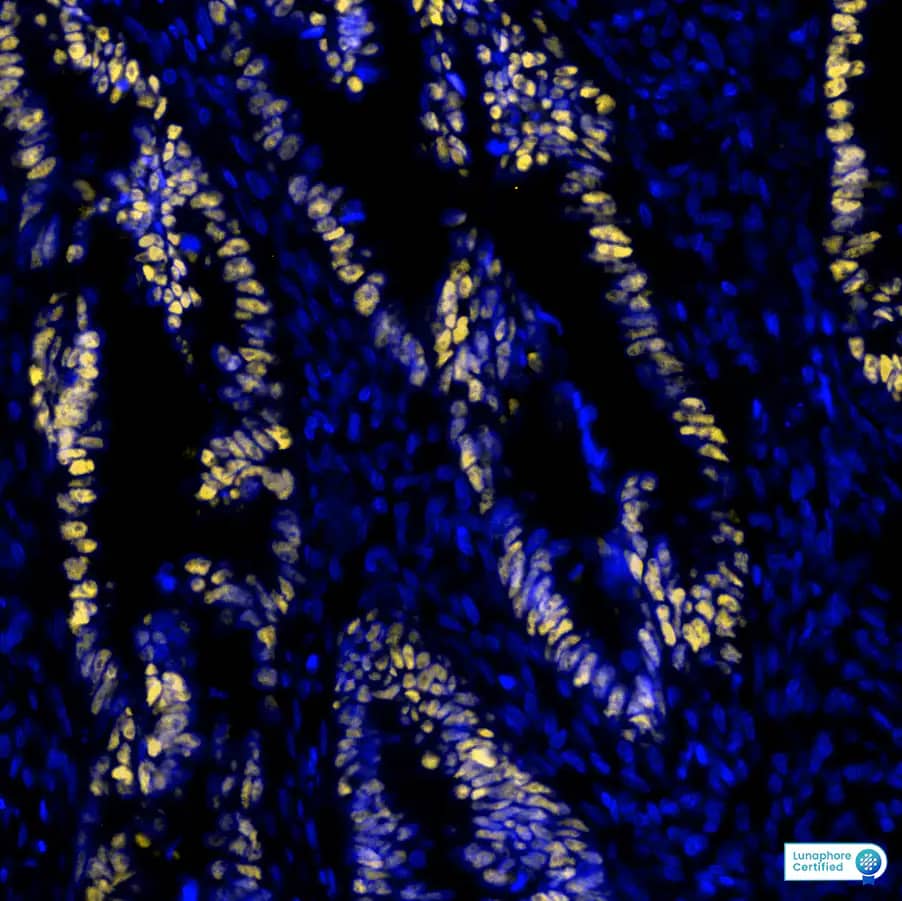

p53 was detected in immersion fixed paraffin-embedded sections of human Colon Tumor using Mouse Anti-Human p53 Monoclonal Antibody at 12ug/mL at 37°Celsius for 8 minutes. Before incubation with the primary antibody, ...read more